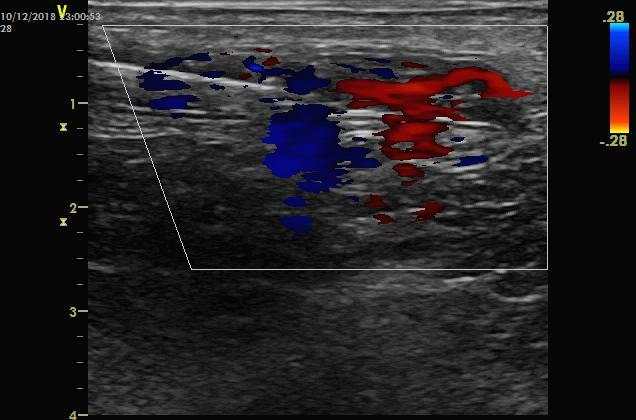

然后经导管内脉冲式注射溶栓药液。如下图。脉冲式注射的目的是希望喷射的药液有一定冲击力,对血栓有机械碎裂作用,这种作用在使用多侧孔溶栓导管更为明显。

一边缓慢回撤导管,一步注射,直到鞘管部位。可以使用彩色多普勒观察药液喷射的信号。